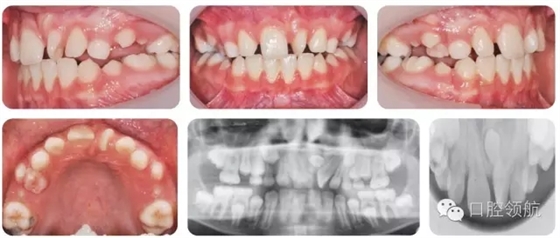

10歲的男性患者,由全科牙醫(yī)轉(zhuǎn)診。該患者健康情況良好,主訴是上前牙不美觀(圖2.16)。

圖2.16

● 混合牙列,III類切牙關(guān)系,前牙覆減小但未出現(xiàn)開牙合。

● 雙側(cè)磨牙1/2牙尖II類關(guān)系。

● 上中線左偏。

● UL1近中腭側(cè)旋轉(zhuǎn)。

上頜中線處存在未萌出的多生牙。

上頜中線處多生牙。形態(tài)為錐形,倒置??赡苁钦卸嗌馈?p style="text-indent: 2em; text-align: left;">該病例怎樣治療?